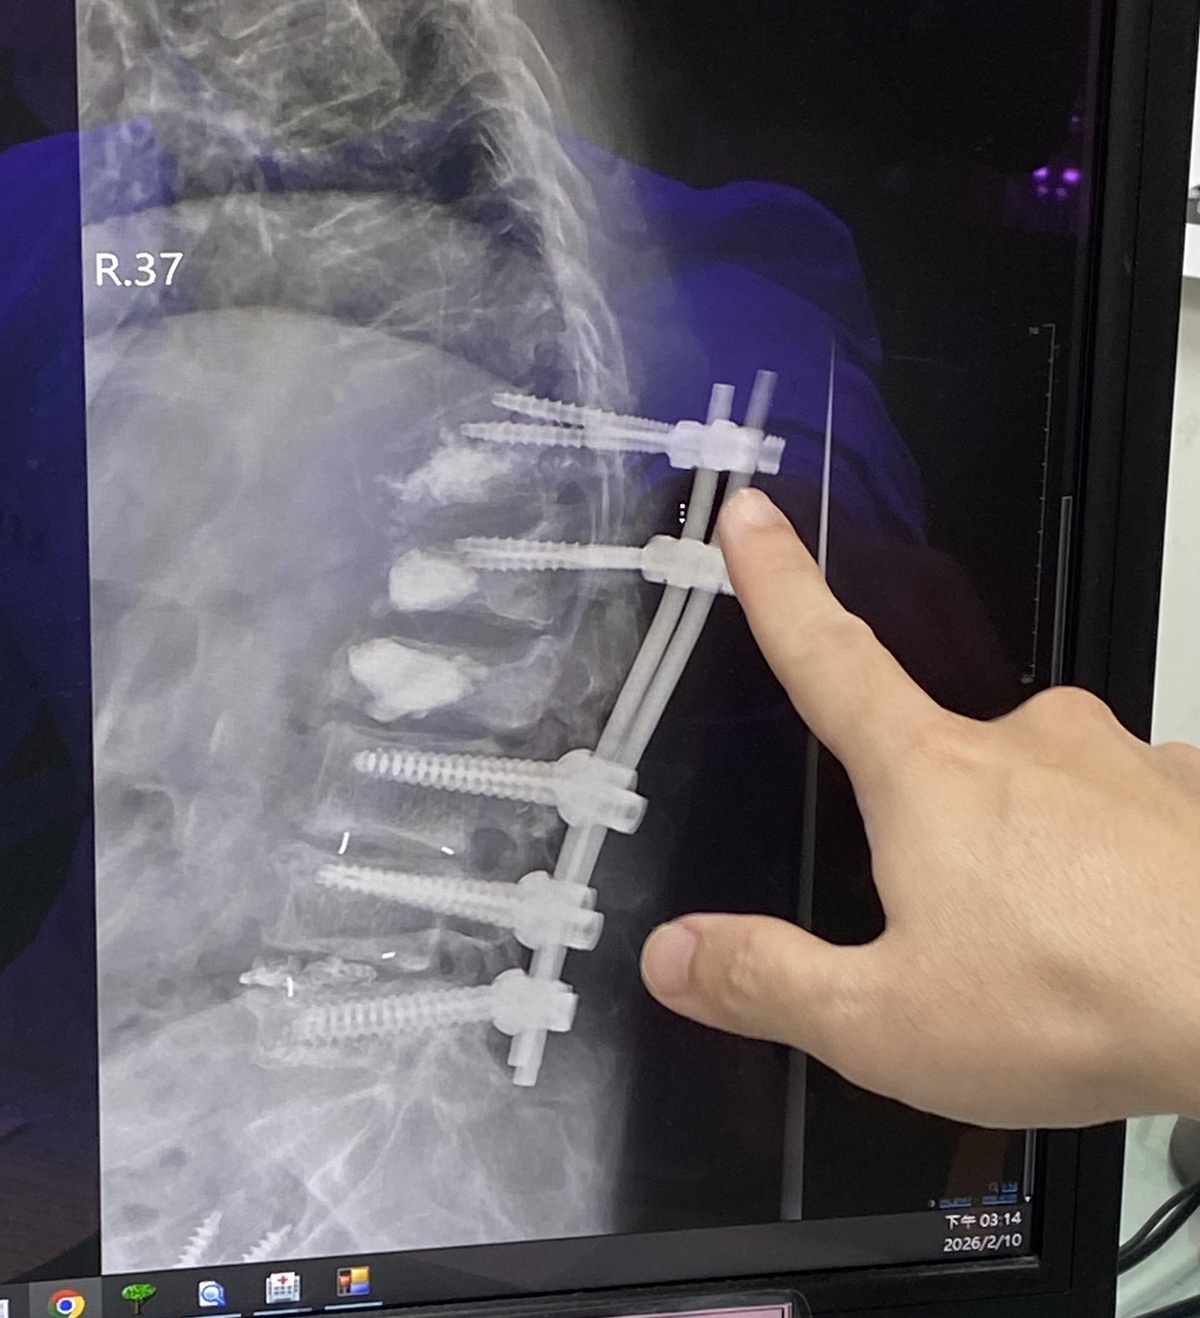

婦人表示,因腰痛、背痛,做了許多治療,也吃止痛藥、復健效果有限,仍背痛難耐在某醫院骨科醫師建議下,動了手術,然而手術後依舊疼痛,之後又連續動四次手術,也灌了骨水泥。手術後,背痛程度仍然劇烈,而且漸漸就越來越不能走。她躺著的時候輾轉反側,翻身也痛,正躺也痛;要走路、站也站不住,肩膀及右側髖關節也曾因跌倒骨折。

呂醫師說,患者剛來門診時,是由她先生推輪椅,把她推到床邊,她掙扎地爬到診療床上。呂醫師翻開患者背部看到五到八道疤痕,都是手術後留下的,疤痕硬的程度,用一般針灸幾乎刺不進去。像那種疤痕,僵硬也會造成疼痛,造成肌肉協調異常,這一部分是用針刀處理,因為一般的針已經刺不進去了。